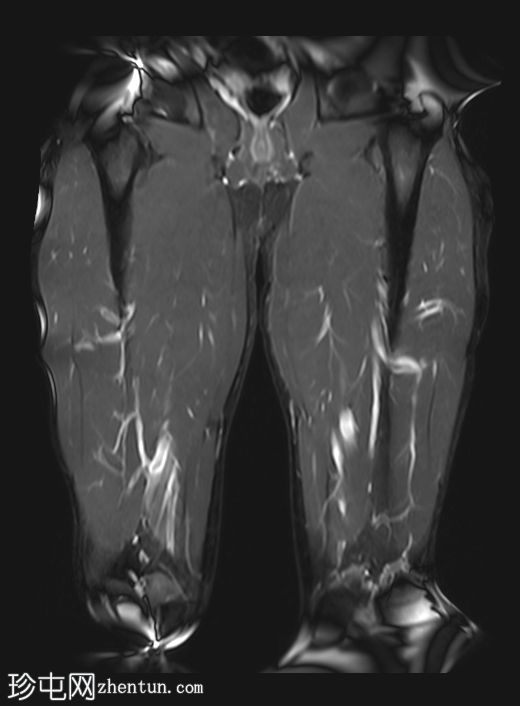

冠状位

T1加权像

左侧股直肌近端肌腱交界处可见异常高信号,向远端延伸约至肌长一半。

可见清晰的充满液体的分离平面,呈“靶心征”,将双羽状间接头与浅表单羽状直接头分隔开,呈现出股直肌脱套样损伤的特征性影像

间接头肌纤维与近端肌腱保持连续,未见肌腱断裂或明显回缩。

可见轻度肌间及筋膜周围水肿。病例讨论